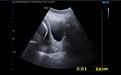

门诊产检发现宫颈管短、内口扩张

就在白女士及家人觉得可以松一口气的时候,孕21+5周在产科于雪梅主任门诊例行产检时,彩超检查发现宫颈管短,只有0.5cm(孕期正常宫颈长度应大于等于3cm),内口扩张约1.5cm,诊断为宫颈机能不全,情况紧急,如病情进一步发展,可能随时发生胎膜早破导致2个胎儿流产夭折。白女士既往宫外孕病史、近高龄、试管婴儿、双胎妊娠,如果此次妊娠流产了,以后很可能失去做母亲的机会,面对紧张地手足无措的白女士及其家属,于雪梅一边安慰着他们,一边告知目前最好的办法是行紧急宫颈环扎术,关闭“生门”,“兜”住胎儿,但手术也有缝针刺破羊膜囊导致手术失败的风险,因为白女士一直在城阳区人民医院产科产检,她和家属表达了对产科团队的高度信任,于雪梅立即电话通知方建红主任,并开通绿色通道,紧急收入院,完善相关检查同时予以保胎抑制宫缩治疗。方建红主任立即组织产科团队成员进行术前讨论、知情沟通、联系手术室,做好紧急宫颈环扎术前准备。